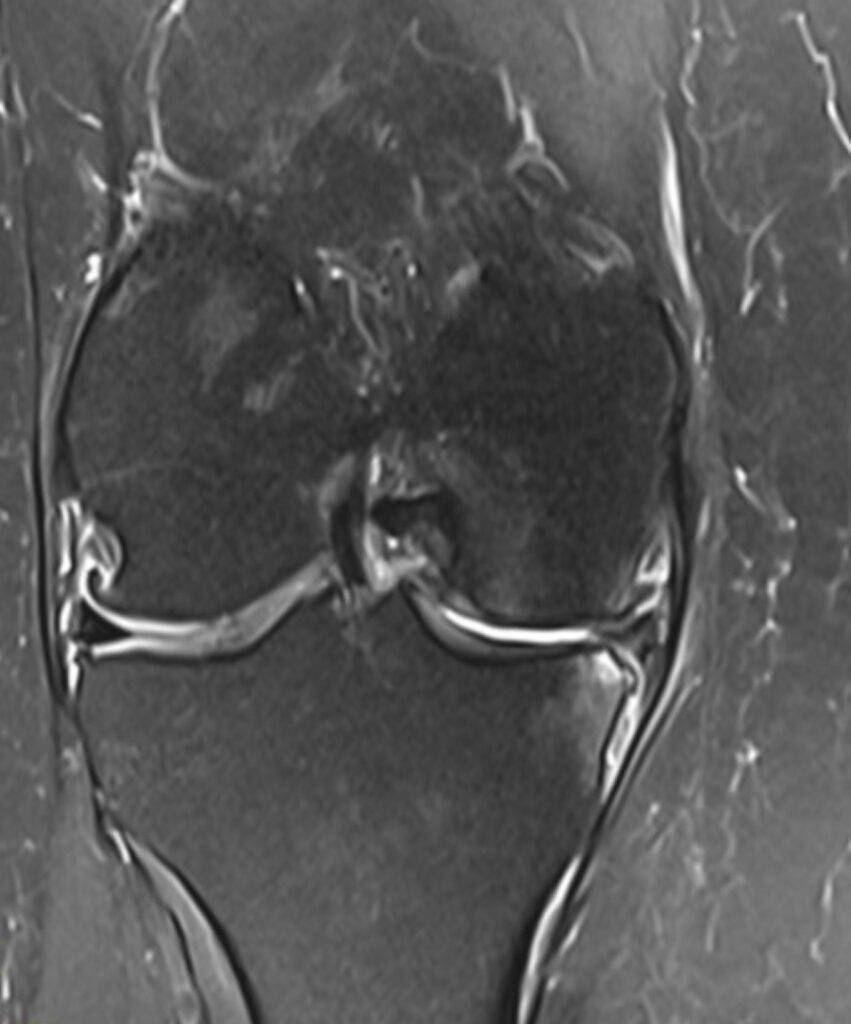

MRT Knie Frontalansicht

Eine MRT Knie ist eine der häufigsten durchgeführten MRT-Untersuchungen. Schmerzen im Knie können viele Gründe haben, da das Knie aus einem Gelenkkomplex besteht. Diesen Gelenkkomplex kann man in einer Knie MRT detailliert darstellen, um präzise Diagnosen zu erzielen. Das Knie kann Verletzungen insbesondere beim Sport, aber auch im Alltag erleiden.

Zudem ist es möglich, Aussagen über den Zustand des Meniskus (Knorpel zwischen Oberschenkelknochen und Schienbein), der Bänder und des Knorpels des Kniegelenks zu machen, sowie die Intaktheit der Sehnen, Muskulatur und Knochen abzuklären.

Der Meniskusriss ist eine typische Sportverletzung. Die Lokalisation, die Größe als auch die Form des Risses lassen sich anhand der Aufnahmen analysieren. Diese sind für die anschließende Therapie von großer Bedeutung

Kniearthrose lässt sich im Rahmen einer MRT-Untersuchung ebenfalls genauer analysieren. Sind sogenannte „weiße Stellen“ im MRT zu erkennen, handelt es sich hierbei möglicherweise um Zeichen einer Flüssigkeitsansammlung und könnte ein Hinweis auf ein Knochenmarködem sein.